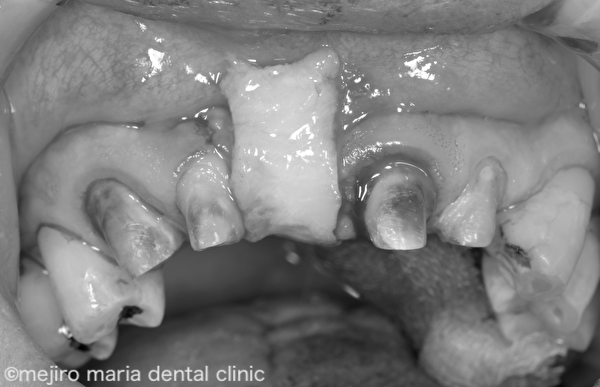

上記Before画像を見ると、欠損部である右上1の歯肉が大きく陥凹しているのがわかります。この凹んだ歯肉に合わせてブリッジが作製されていたために機能的、審美的な障害が生じていました。

今回は失われた歯肉のボリュームを回復するために、結合組織移植術(CTG)を選択しました。口蓋(口の上側の部分)から採取した結合組織を歯肉の凹んだ部分に移植し、ボリュームアップさせました。移植術、と聞くと大掛かりな外科手術を想像されるかもしれませんが、最近では非常に小さいミニマルな術野で処置を行う事ができるようになり、患者様の術後の疼痛もほとんどありません。傷口が目立つ心配も全くありません。

上記After 画像を見ると、歯肉形態が概ね生理的な状態に改善している事がわかります。この状態で歯肉の形態を整えながら治癒を待ち、約6ヶ月後に適合の良いブリッジを作製し装着しました。